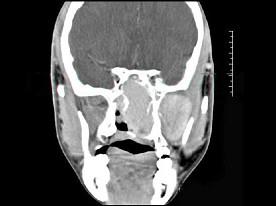

男性,19岁,左侧鼻腔反复出血一年余,CT、MRI扫描如图所示,请选择最可能诊断 ( )

答案: E